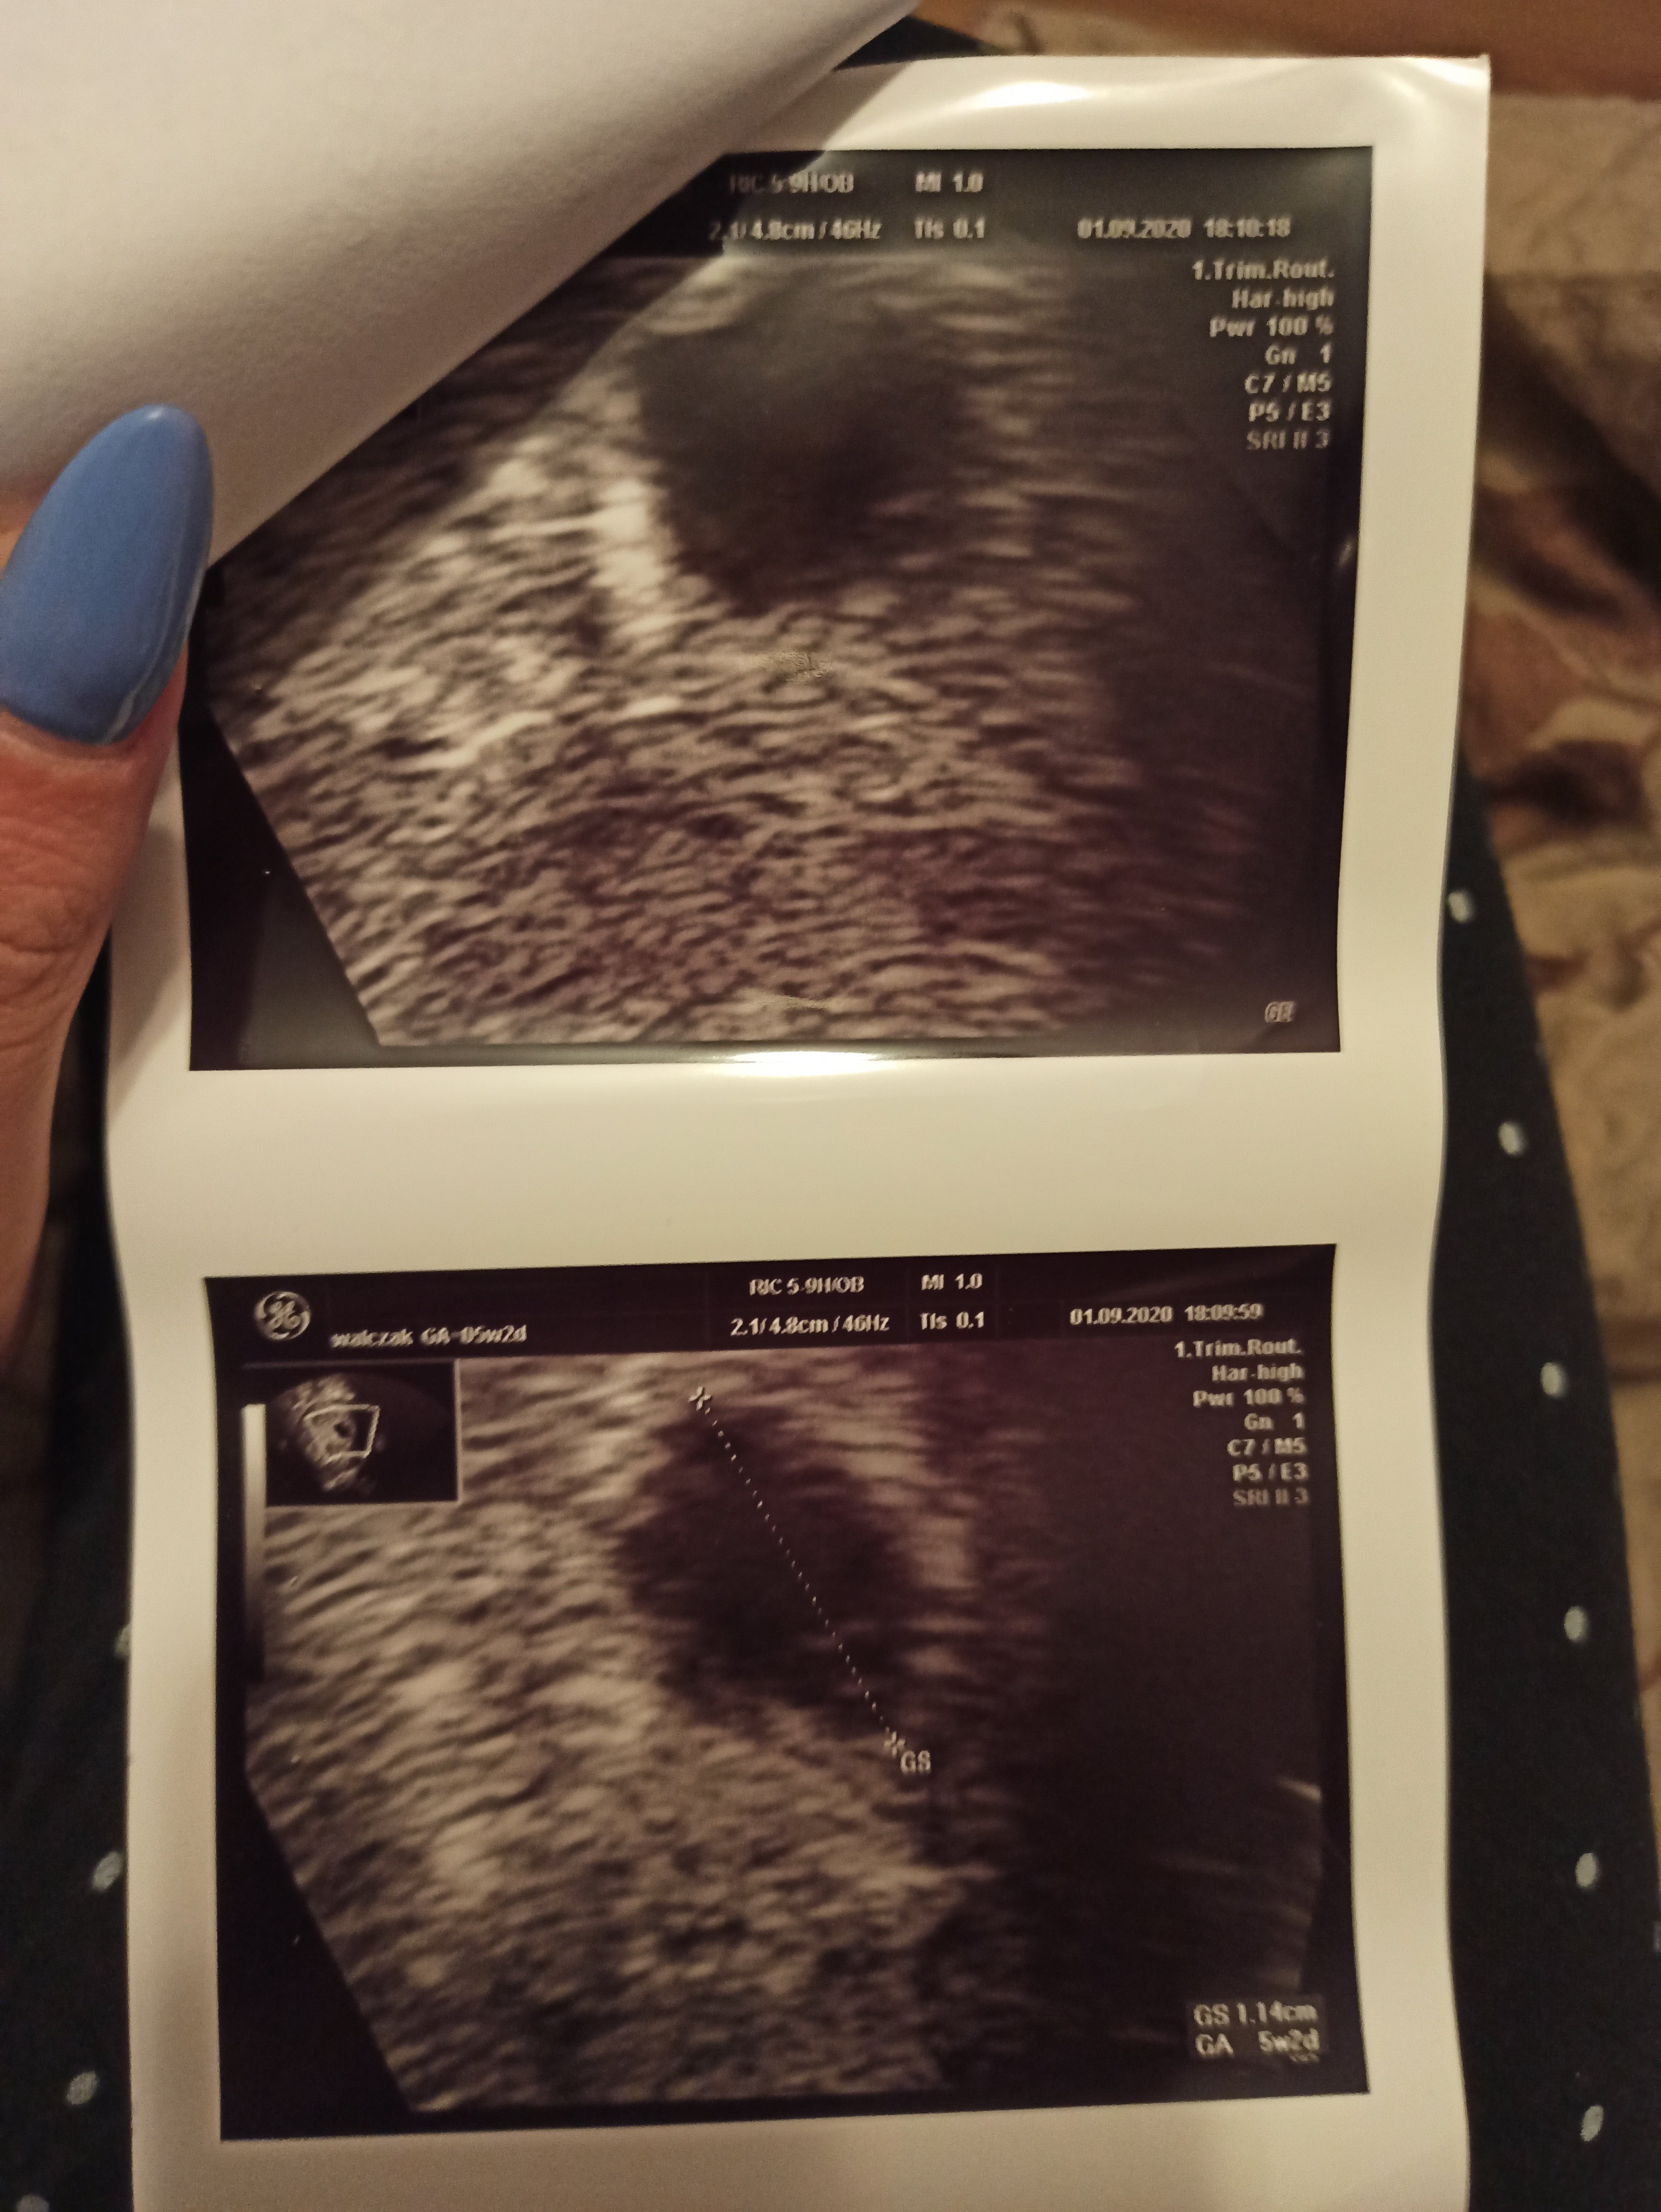

Pęcherzyk 1,61cm. Martwię się czy wszystko w porządku. Jedyny dzień w jakim działaliśmy to 1 sierpnia. Lekarz kazał mi przyjść 24 września, ale dał mi już wszystkie skierowanie na badania.Zobacz załącznik 1171992

Według 5t to masz bardzo dobry rozmiar pęcherzyka, zaraz ja wstawię swoje zdj. A jakie będziesz robić badania?

Ja byłam w 5t2d i był tylko pęcherzyk. Mam po Tobie wizytę 15.09 będę wtedy w 7t też się nie mogę doczekać. Ja najpierw stresowałam się na tą pierwsza wizytę a teraz już rozmyślam o tej drugiej, czas mógłby szybciej lecieć